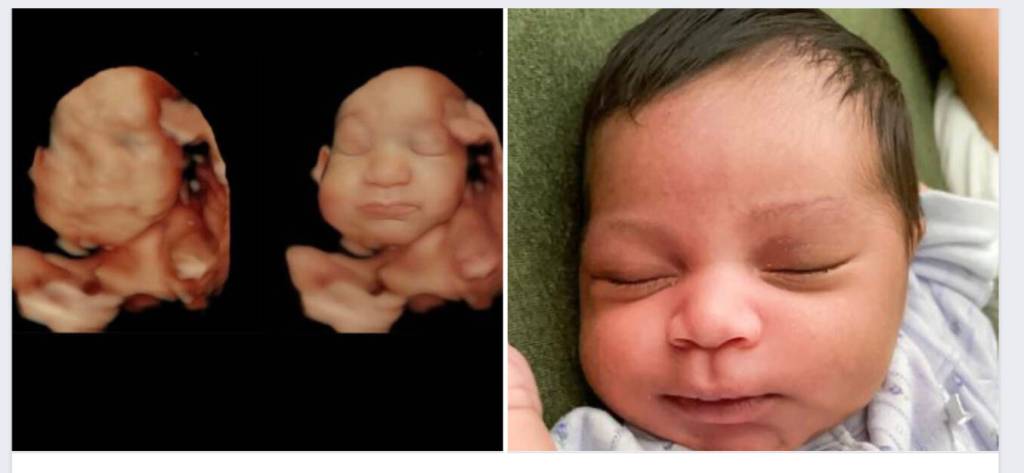

Many will remember the first time they ever saw a 2D ultrasound scan of their unborn sibling as a tender and exciting moment in their childhood. For some kids however, the excitement is quickly followed by a feeling of confusion as they try to make out the traits of a baby in what may seem more like bad chalk art.

Now, families on Whidbey Island can share with their kids the joy of seeing their child in detail, creating a stronger emotional connection with the baby. In May, Sonographer Kulvinder Kaur opened Island County Ultrasound, the only business on the island that offers color images and videos of fetuses in 3D, 4D and 5D, in addition to the 2D scans.

According to Kaur, 3D scans are still images, 4D scans come in both photo and video format, and 5D scans allow her to adjust the light to better see the baby. Unlike 2D ultrasounds, which show the baby’s organs and skeletal structure in black and white, these options make the baby look more realistic.

Located at 902 NE Center Street in downtown Coupeville, Island County Ultrasound also offers parents the chance to further enhance their baby’s images after the ultrasound session, adding more detail to their features as if they’re immortalized out of the womb. Sometimes, this makes for funny moments — like a baby sticking his or her tongue out.